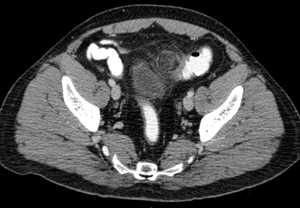

В ходе операции установлено, что ранее ущемленный большой сальник фиксирован в обоих внутренних паховых кольцах (см. рисунок). Рисунок 1. Внутреннее ущемление тонкой кишки (схема). 1 - тонкая кишка; 2 - брюшинный тяж; 3 - участок некроза брюшинного тяжа; 4 - правое и левое внутренние паховые кольца; 5 - ущемленный большой сальник; 6 - передняя брюшная стенка. Под сальником продольно на протяжении ущемлена петля тонкой кишки, что вызвало частичную кишечную непроходимость. Сальник рассечен, проходимость кишки восстановлена. При дальнейшем осмотре выявлена аномалия развития - брюшинный тяж, идущий от корня брыжейки тонкой кишки к подвздошной кишке и к основанию червеобразного отростка. Брюшинный тяж на участке ущемления некротизирован на протяжении 10 см, при этом серозная оболочка тонкой кишки осталась интактной. Инфильтрированные с налетом фибрина участки большого сальника резецированы в пределах здоровых тканей. Червеобразный отросток деформирован, стенки утолщены, верхушка изогнута дугой. В связи с вторичными изменениями выполнена типичная аппендэктомия. Через прокол в правой подвздошной области в малый таз подведена дренажная трубка. Рана зажила первичным натяжением.